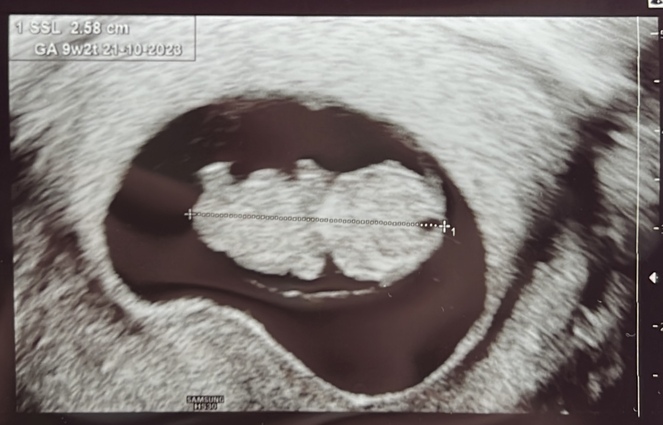

Unsere Mamas haben es erfahren! - Tagebücher aus der Schwangerschaft von Jenny aus Hamburg

Eine neue wunderbare, aufregende und vielleicht auch lang erwartete Lebenszeit beginnt. Für unsere Tagebücher-Blogs haben wir immer 3-4 schwangere Frauen in unterschiedlicher Schwangerschaftsphase, die in freudiger Erwartung über jede Woche dieser spannenden Zeit schreiben, uns und die vielen tausend Follower:innen daran teilhaben lassen und damit unvergessliche Momente schaffen.